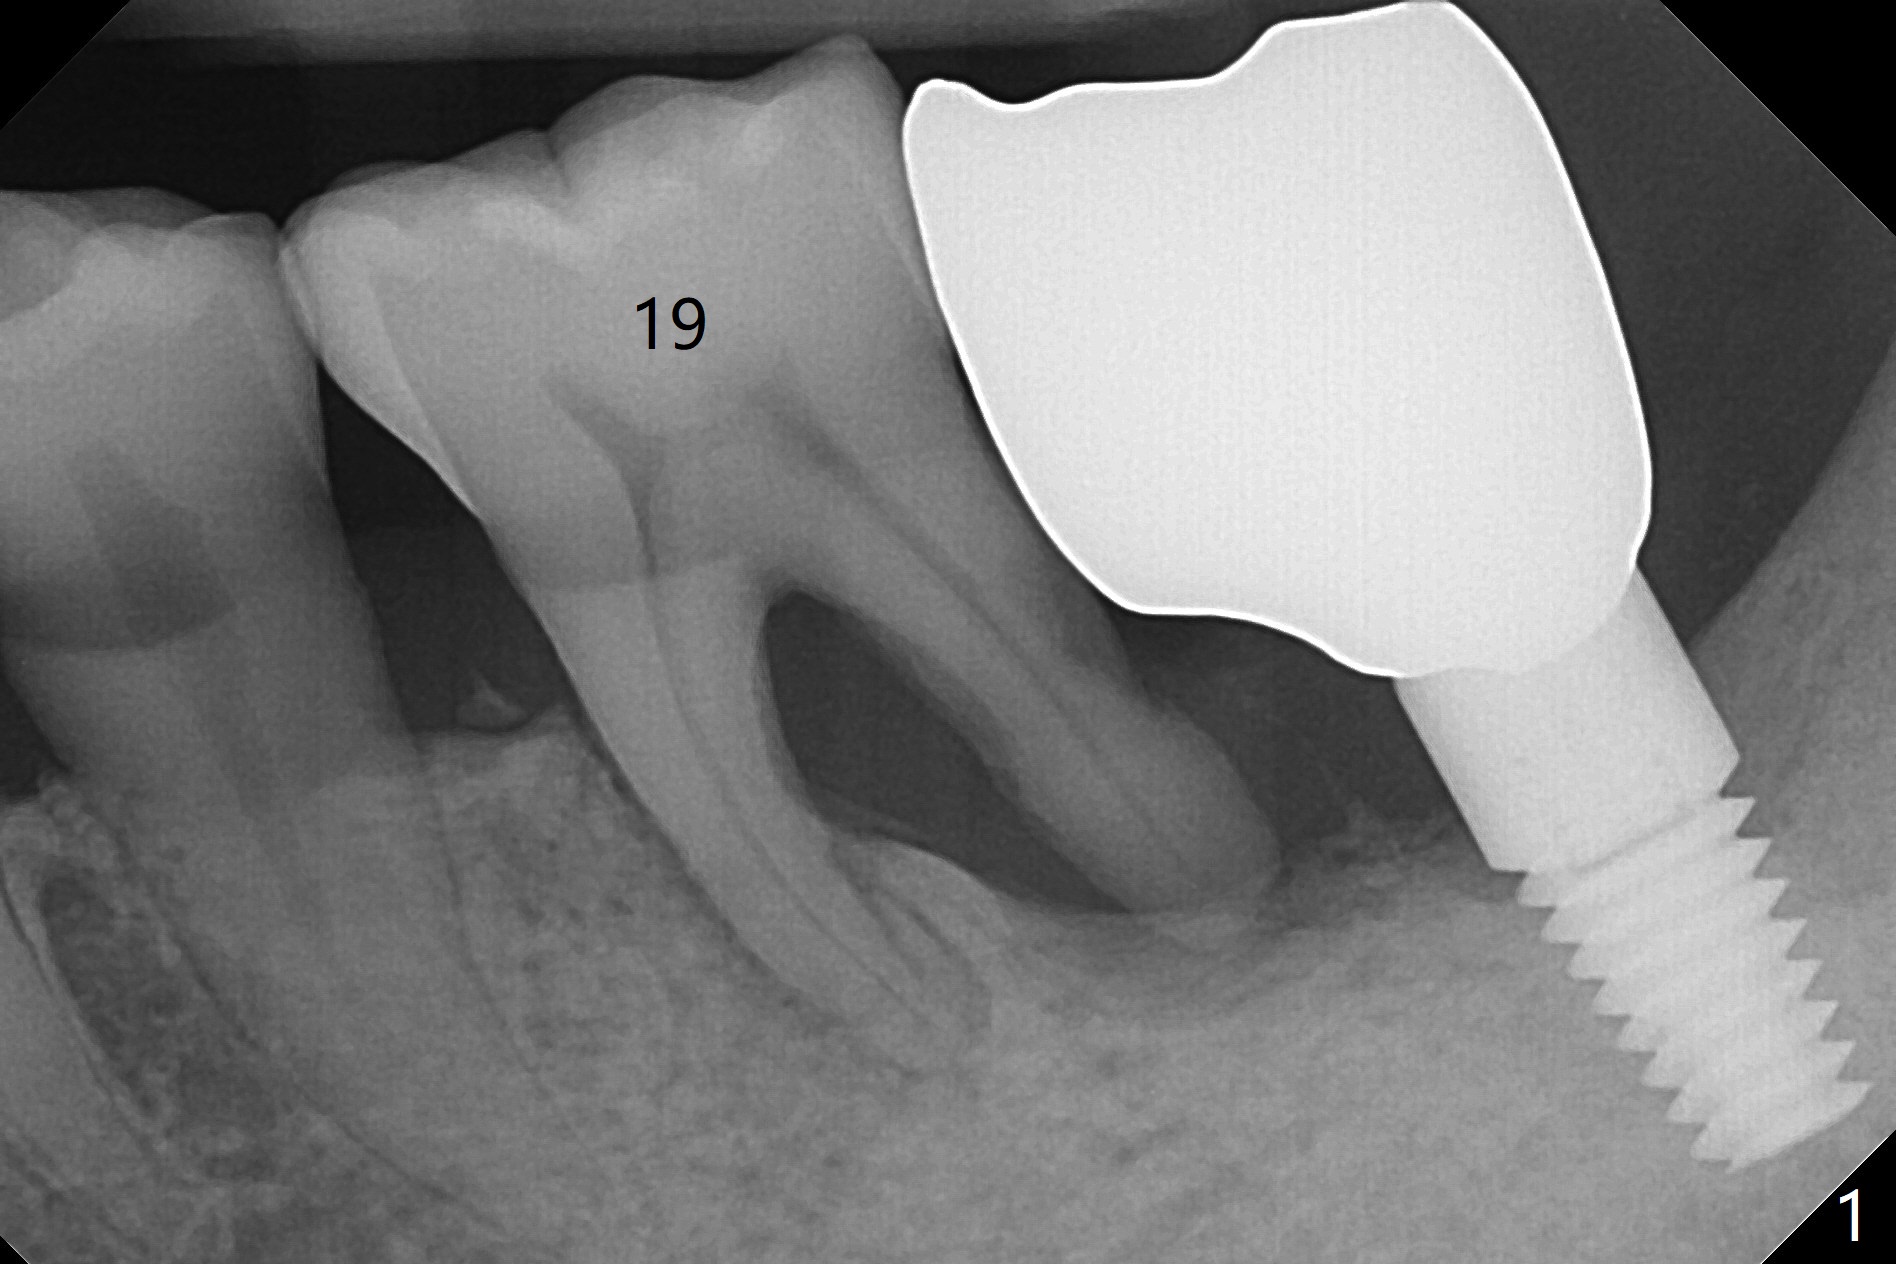

A 66-year-old man develops severe pain at night at #19 seven months post cementation at #18 (Fig.1). There is a piece of the gingiva over the septum, noted after extraction. The mesial and distal sockets are small, being able to hold Vanilla allograft (Fig.2 *), followed by pieces of Collagen plug and suture.